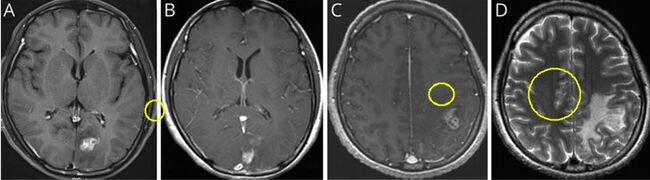

이번 연구는 서울대병원에 내원한 40대 여성 환자를 대상으로 이루어졌다. 환자는 심한 두통과 구토 증세로 병원을 방문했으며, 초기 뇌 자기공명영상(MRI)에서 좌측 후두엽에 불규칙하게 조영된 종양성 병변이 발견돼 뇌종양이 의심됐다. 의료진은 수술을 권유했지만, 환자는 증상이 일시적으로 호전되자 치료를 거부하고 퇴원했다.

7개월 후, 환자는 다시 극심한 두통과 전신 발작으로 병원을 방문했다. 후속 MRI에서 병변이 좌측 후두엽에서 좌측 두정엽으로 이동한 것이 확인됐고, 이 병변 이동은 스파르가눔증의 대표적인 진단 단서가 됐다.

(A) 초기 뇌 MRI에서 좌측 후두엽에 조영증강된 종괴가 관찰됨 (B) 3개월 뒤 시행한 뇌 MRI에서 좌측 후두엽의 종괴가 사라짐 (C) 8개월 뒤 시행한 뇌 MRI에서 좌측 두정엽에 새롭게 조영증강된 종괴가 발견됨 (D) 좌측 두정엽 종괴 주변에 심한 뇌부종이 동반된 모습이 확인됨/ 서울대병원 제공그 결과, ELISA 검사와 뇌척수액(CSF) 검사에서 스파르가눔증 항체가 검출됐으며, 정위적 생검에서는 염증성 육아종이 확인됐다. 이후 개두술을 통해 살아있는 스파르가눔증 유충을 성공적으로 제거했다. 수술 과정에서 기생충이 살아 움직이는 모습이 영상으로 기록됐다.